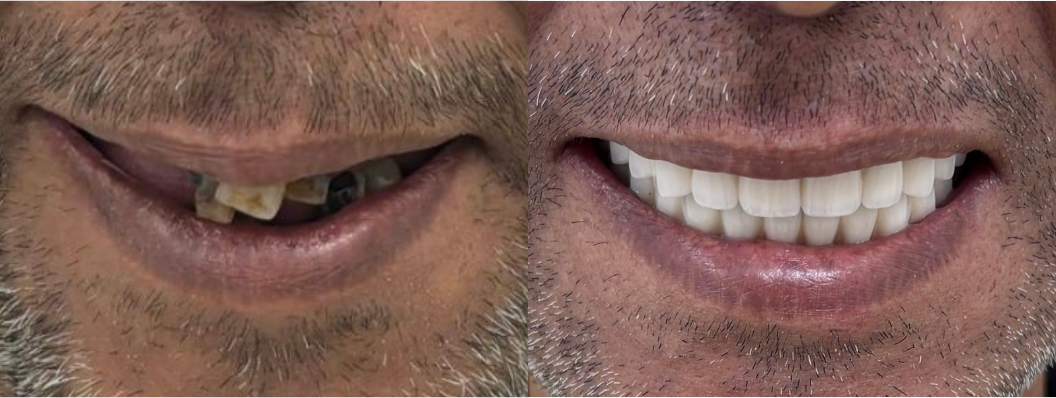

Full mouth rehabilitation cases

A full mouth rehabilitation is a comprehensive restoration of all teeth, aiming to bring back both function and aesthetics.

When replacing worn or damaged implants, achieving a balanced, natural look requires careful planning and precise execution. With the right approach, I focus on rebuilding the bite and creating a beautiful, harmonious smile that feels as natural as it looks.